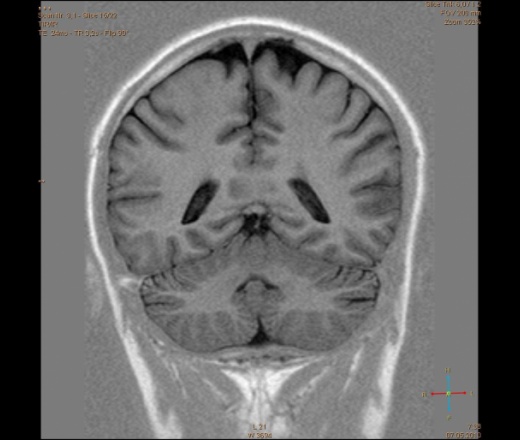

ID:56081

Болезнь Маркиафавы-Бигнами посмотри. На мой взгляд подходит.

Я заметил только 1 очаг в валике мозолистого тела. А для б-зни Маркиафавы-Бигнами более характерно несколько очагов дегенерации, в том числе и в полушариях.

По моему просто опухоль, м.б. глиобластома.

Для болезни Маркиафава-Биньями считается патогноманичным центральная дегенерация мозолистого тела.

"Болезнь Маркиафава-Биньями – Болезнь Маркиафава-Биньями (Marchiafava, Bignami)- синдром при хроническом алкоголизме: энцефалопатия в форме центрального некроза corp.callosum (иногда и других комиссур). "

Я не против, действительно м.б. "Болезнь Маркиафава-Биньями". Особенно если нет динамики.

Но диф. ряд должен быть с опухолью. И если есть негативная динамика, тогда больше похоже на то, что в моз.теле не дегенерация, а "плюс-ткань" - обьемное образование. За октябрь сканов нет?

К сожелению первое исследование проводил ни я, а моя коллега, но контроль был за мной. Уже при первом исследовании, опухолевую принадлежность можно взять под сомнение, по скольку, даже допустим возьмем глиобластому это злокачественная опухоль из глиального ряда, т.е. должен быть тумор+отек=масс-эффект, ни того и не другого нет, ко всему этому сама локализация это валик мозолистого тела, а ни гемисфера, компенсации ни должно быть ни какой, клиника должно быть молниеносной и нарастающей.

Ко всему выше перечисленному могу добавить, видимо мою коллегу сомнения гложили, она провела исследование с контрастированием и получила тот же результат.